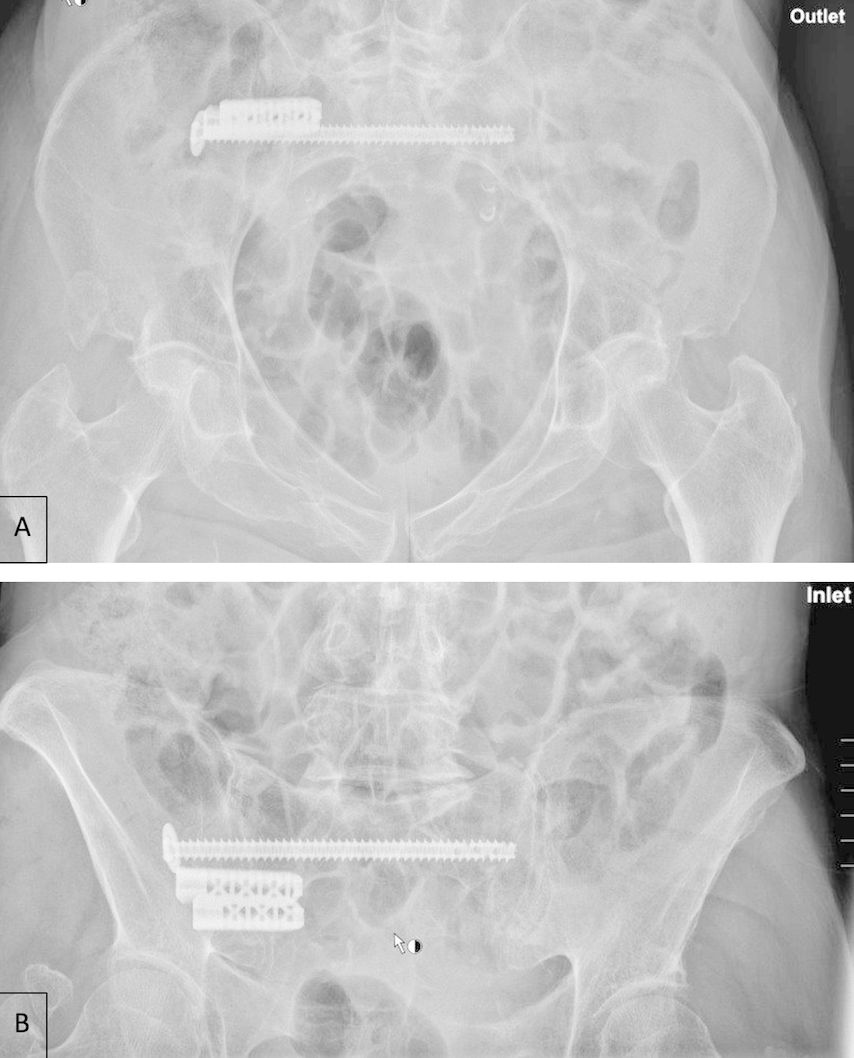

Nach Vorstellung der Patienten in unserem Traumazentrum Level I mit immobilisierenden und anhaltenden Schmerzen im unteren Rücken nach erfolgloser konservativer Behandlung wurde im Falle einer Typ-II-Fraktur eine elektive chirurgische Stabilisierung mittels iFuse in Kombination mit transiliosakralen Schrauben (TIS) (TISTM-Schrauben, Königsee Implantate GmbH, Allendorf, GER) durchgeführt (Abb. 1).

Abb. 1: Postoperatives Röntgenbild (A: Outlet, B: Inlet) einer 86-jährigen Patientin mit einer FFP Typ IIb rechts nach frustraner konservativer Therapie und daher nun chirurgischer Stabilisierung mittels iFuse® in Kombination mit transiliosakralen Schrauben (TIS); postoperativ signifikante Schmerzverbesserung mit rasch möglicher Mobilisierung

Bei Vorliegen einer FFP Typ IV wurde eine sofortige Operation mittels iFuse und TIS sowie additiver Stabilisierung des vorderen Beckenrings durch retrograde Schraubenfixierung oder winkelstabile Plattenosteosynthesen durchgeführt. Kein Patient litt an einer FFP Typ III. Alle Patienten wurden sowohl prä- als auch 3 bis 7 Tage postoperativ einer Bewegungsanalyse unterzogen. Hier erfolgte dann die Erhebung des Schmerzniveaus mittels Visueller Analogskala (VAS) in Ruhe und bei Bewegung.